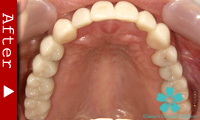

数本の歯を失った場合

この場合もインプラントが理想的な解決法となります。数本のインプラントを歯のない部分に入れ、これを土台としてヘッド部にブリッジをかぶせます。